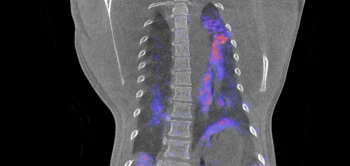

Op Wereld Obesitasdag staan we stil bij de problemen die bij overgewicht en obesitas komen kijken.